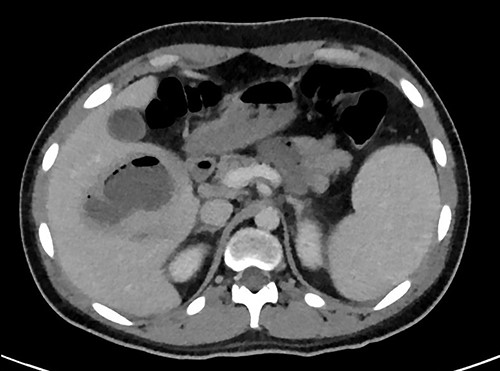

A full lab panel was ordered and revealed a total bilirubin of 1.1, direct bilirubin 0.5, lactate dehydrogenase 196, alkaline phosphatase 80, aspartate transaminase 46 and alanine transaminase 58. A computed tomography (CT) angiographic scan of the chest, abdomen and pelvis revealed the presence of a rim enhancing fluid collection in hepatic segment V with internal gas and containing a metallic foreign body, measuring 8 × 5 cm and consistent with abscess formation (Figs 2–4). The linear tract of the bullet in the right iliac crest was visualized in the CT as well.

Transverse plan of the CT showed the bullet lodged in segment 5 of the liver.